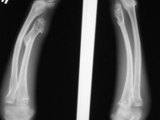

Multiple exostoses-forearms

Multiple exostoses-forearms